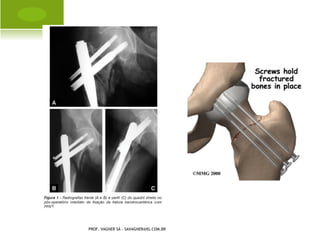

T RANSTROCANTÉRICA    E

ACETÁBULO

PROF. VAGNER SÁ - SAVAGNER@IG.COM.BR

SUBTROCANTÉRICA

DIÁFISE